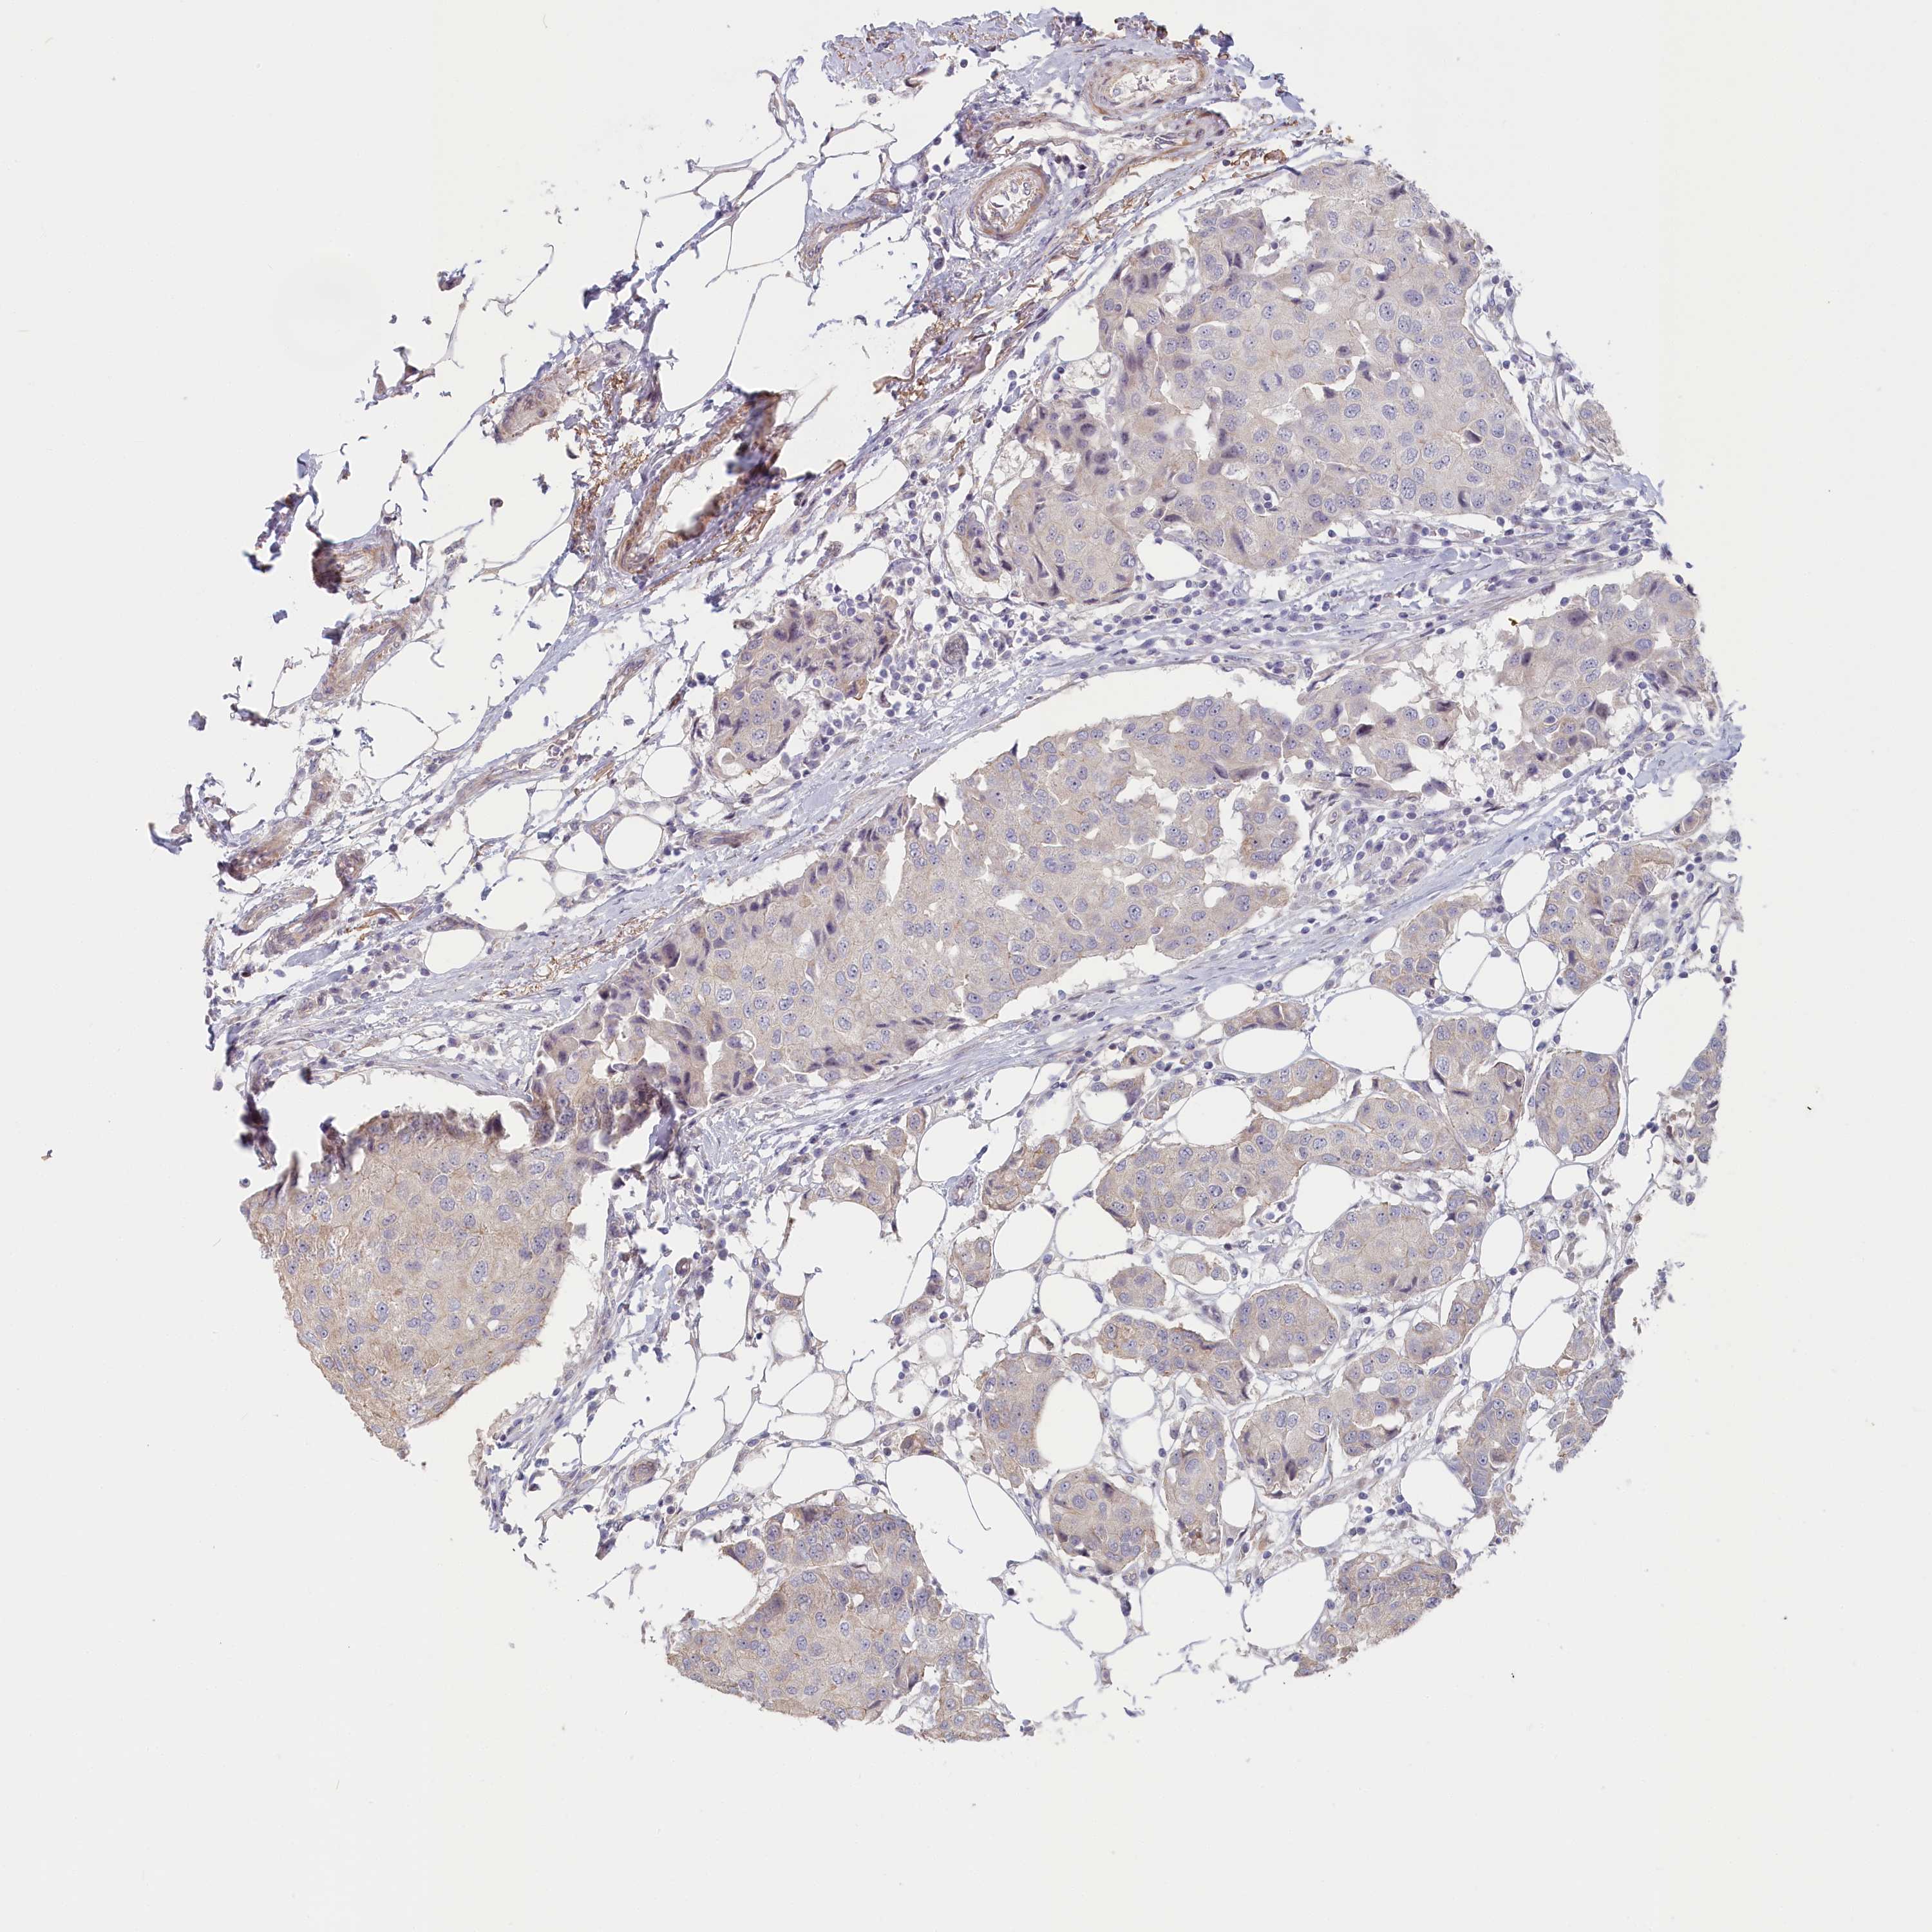

CANCER BREAST CANCER Show tissue menu

BRCA TCGA BRCA VALIDATION PROTEIN EXPRESSION

ANTIBODIES

AND

VALIDATION